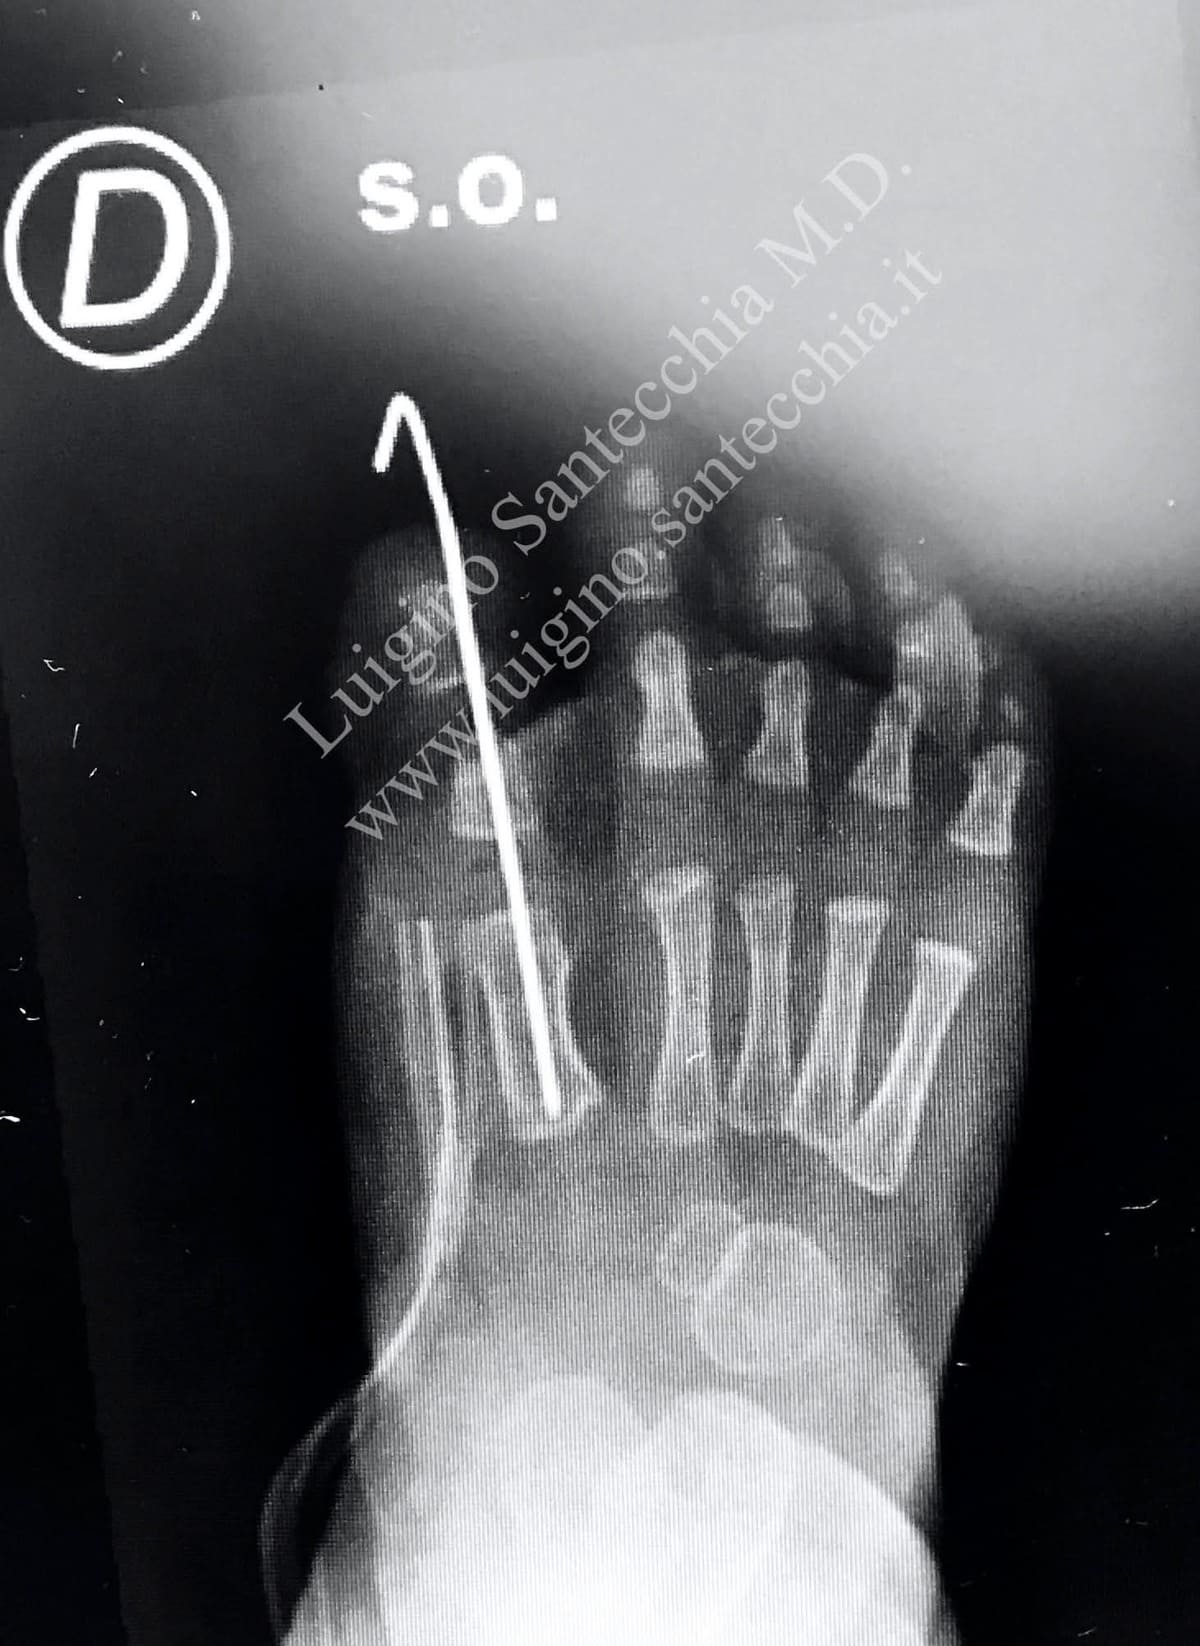

Before Surgical treatment